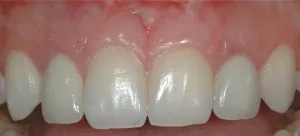

Antes y después de dos implantes de incisivos